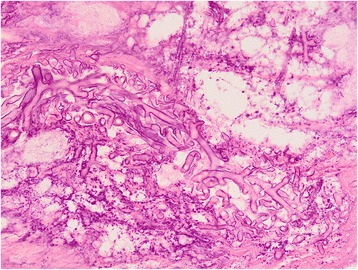

On anterior rhinoscopy all patients had black blood stained debris in the region of inferior and middle turbinate along with necrosis on endoscopy. Direct examination was performed after PAS staining. Tissue specimens for culture were obtained from all cases. The culture was made on Sabouraud chloramphenicol medium with and without cycloheximide. In ten cases, the diagnosis of mucormycosis was based on positive histopathological findings for mucormycosis (Fig. 3). In three cases, Mucor spp. was isolated from tissue cultures and it was pathologically verified in all patients of mucormycosis. The histological examination revealed large non-septate mycelial filaments, sometimes branched at a right angle with images of angioinvasion within necrotic and inflammatory material.

Fig. 3.

Nasal biopsy showing mycelial filaments of variable thickness and necrosis (PAS;×200)